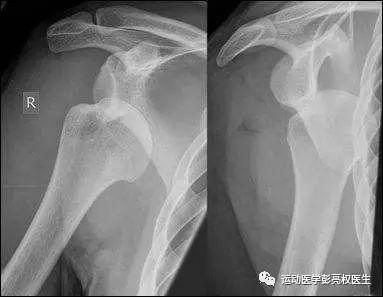

(2)每一次的脱位复发都会导致新的损伤,如盂唇的损伤(Bankart损伤),肩胛盂前缘骨性缺损,肱骨头后上方压缩骨折(Hill-Sachs损伤),盂肱下韧带肱骨端损伤(HAGL损伤),肩袖损伤等等,结果是关节囊和韧带越来越松弛,关节软骨和盂唇的损伤也越来越重,导致手术后的效果也越来越差,或本来可以微创完成的手术必须切开做,本来只需修复软组织的后来不得不植骨。根据我们深圳市二医院运动医学科的经验,一般脱位在5-10次以上的患者不仅有明显的软组织损伤,还合并严重的骨性损伤。而一旦动骨头,患者术后容易遗留部分活动度丧失,有的甚至因为骨的损伤过于严重而需要换个人工关节,不但增加了花费,关节功能也丧失了不少,以后还会有关节松动需要翻修的风险。